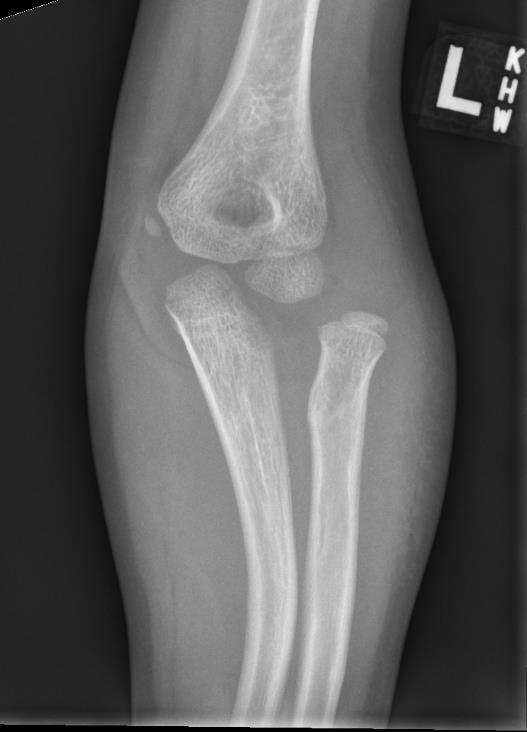

Case 1. Missed Monteggia, injury 6 months ago